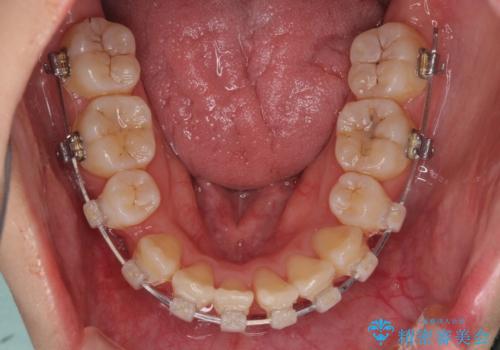

- 矯正装置

- 審美装置

移動量が多かったため、治療期間は通常より半年~1年ほど長くかかりましたが、上下の正中をほぼ同じ位置にまで移動させることができました。